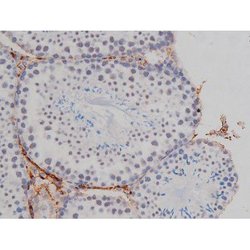

Invitrogen™ Phospho-NPM1 (Thr199) Polyclonal Antibody

Antibody detects endogenous levels of Nucleophosmin only when phosphorylated at Threonine 199.

| Applications | Immunohistochemistry (Paraffin), Western Blot, Immunocytochemistry |